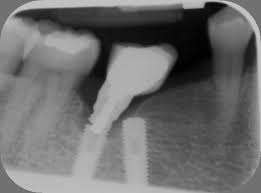

Atrofia ósea alveolar

La atrofia ósea alveolar es la pérdida de hueso en la mandíbula o el maxilar debido a la ausencia prolongada de dientes.

Los pacientes pueden notar que sus encías están hundidas y que las dentaduras no encajan bien.

El tratamiento puede incluir injertos óseos para preparar el sitio para la colocación de implantes.

Falta de hueso para implantes

La falta de hueso suficiente para la colocación de implantes puede ser una barrera para el tratamiento.

Los pacientes pueden ser informados de que no tienen suficiente hueso en la mandíbula o el maxilar para soportar un implante.

El tratamiento incluye técnicas de regeneración ósea, como injertos óseos, para aumentar el volumen óseo.